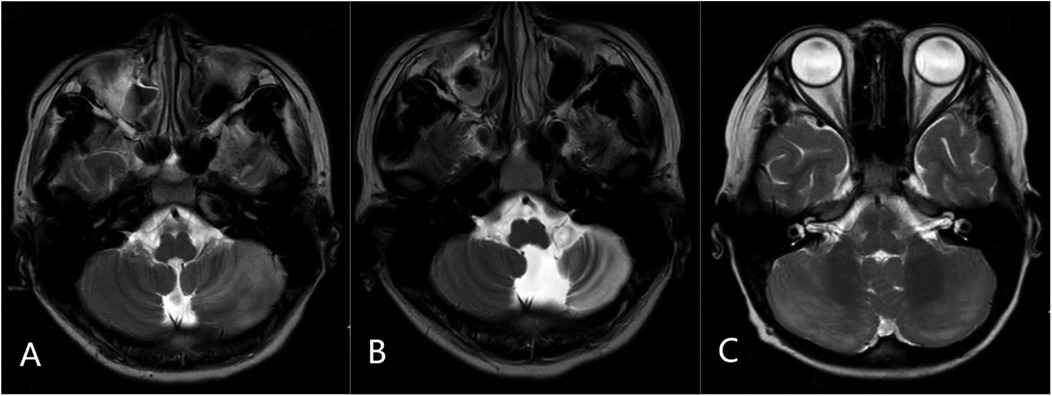

Neuroimaging analysis of 210 cases showed no characteristic abnormalities in most APCA patients, with MRIs being either normal or showing non-specific findings. AC cases (n = 21) exhibited cerebellar T2 hyperintensity with swelling (bilateral in 11/21, unilateral in 10/21), including three cases with tonsillar involvement (one showing herniation) and four cases with concurrent supratentorial basal ganglia lesions. Among eight AC cases with follow-up MRI at 1–2 years, three developed cerebellar atrophy; these three patients experienced persistent neurological sequelae, including moderate ataxia in two and significant dysarthria in one. The five cases showing complete radiological resolution had corresponding good clinical outcomes with minimal or no residual symptoms at last follow-up (Figure 2).

Three MRI brain scans labeled A, B, and C. (A) axial T2-weighted image showing diffuse hyperintensity and swelling in the left cerebellar hemisphere. (B) Follow-up axial T2-weighted image at 2 years in the same patient demonstrating left cerebellar atrophy. (C) Axial T2-weighted image from another patient showing bilateral cerebellar diffuse hyperintensity with swelling.

Figure 2. Representative MRI findings in acute cerebellitis (AC): (A) axial T2-weighted image showing diffuse hyperintensity and swelling in the left cerebellar hemisphere. (B) Follow-up axial T2-weighted image at 2 years in the same patient demonstrating left cerebellar atrophy. (C) Axial T2-weighted image from another patient showing bilateral cerebellar diffuse hyperintensity with swelling.